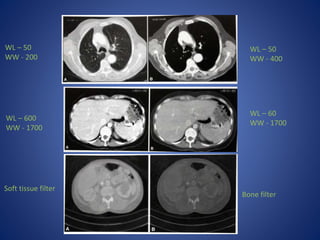

Windowing- the termused for the method of varying density and contrast. Window width-range of CT numbers we select for display Window level-is usually but not always, the central CT number about which the window is chosen

• 44.

Soft tissue filter Bonefilter WL – 50 WW - 200 WL – 50 WW - 400 WL – 600 WW - 1700 WL – 60 WW - 1700